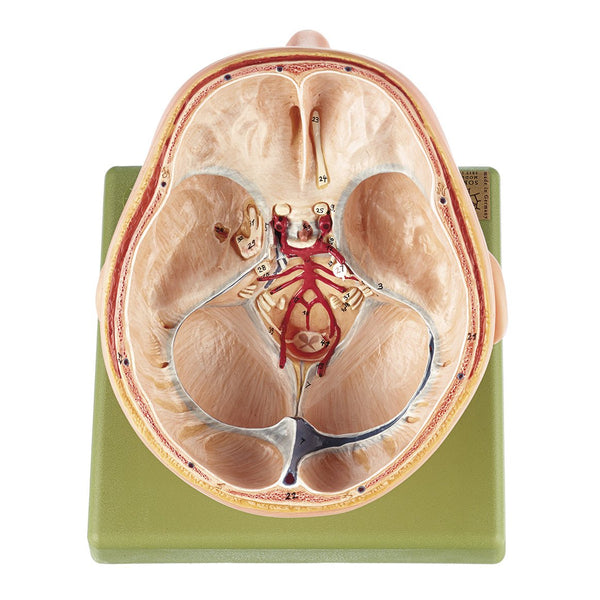

SOMSO Artificial Human Skull - 5 Parts。SOMSO 14-Pieces Model of the Skull with muscles of mastication – GTSimulators.com。SOMSO Artificial Human Skull Model, 2 parts, Removable Lower Jaw – GTSimulators.com。An109様 農薬不使用 玄米 10kg。【SOMSO】ソムソ社製品 実物大の頭蓋骨模型になります。バネのへたりなども無し。袋付きです。*解剖医学の勉強に使いました。サイズ20x13.5x15.5cm#医学部 #歯学部 #薬学部 #看護学部 #整体師 #柔道整復師 #指定校推薦 #解剖学 #予習 #解剖 #骨学 #運動器 #医療系 #医学部浪人 #浪人 #意識あげる。SOMSO Situs of the Base of the Skull。実物大の頭蓋骨模型で【頭蓋冠、頭蓋底、下顎骨の3分解】学術的に精度が高く裂、孔、突起、縫合線、歯も忠実に再現されています。頭蓋骨 模型 ソムソ社製 3分解 QS7/E。骨格模型 人体模型。緩衝材で丁寧に梱包し、付属の袋に入れた上で発送します。NISSIN シンプルマネキン simple manikin。頭部模型 somso社製 Base of the Head。*写真のように縫合部や骨の一部にシャーペンによる記入があります。【美品】等身大 人体模型 約170cm 全身骨格模型 骨格標本。入手困難・通電確認済✨デアゴスティーニ おしゃべりガイコツ ホネッキー1~70巻。*Amazon価格 ¥38,000(2024/11/12現在)*できるだけ綺麗に掃除してお送りします。天然歯牙模型 35種類 歯科技工 歯科